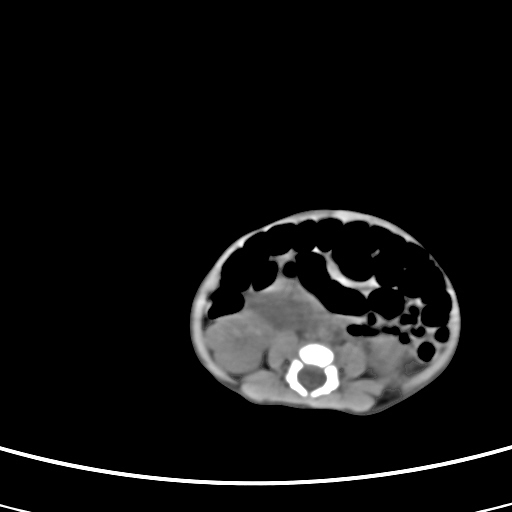

患儿,男性,出生后2天,在胎儿时b超已发现病变,患儿一般情况可。因病变部位偏向于右侧肾上腺区,目前考虑为神经母细胞瘤,不知各位能否支持。

病灶内未见明显脂肪密度。

反对定位在右肾上腺区的说法,那么神经母细胞瘤也可以暂时不予考虑。请看下图:

下面这幅图中,似乎可以见到肿瘤的薄包膜,其后与右肾之间的又是什么东西呢?这关系到肿瘤的定位、定性。我考虑病灶是位于肝十二指肠韧带内的畸胎瘤可能性比较大。请各位老师仔细看一下:

病灶巨大,位于右侧肾上腺区,与周围组织分界欠清,内见不规则钙化影,无明显脂肪组织,首先考虑神经母细胞瘤,但畸胎瘤不能排除。

定位后腹膜,定性:畸胎瘤与寄生胎相鉴别.请传骨窗.发现躯干骨或四肢骨就考虑寄生胎.

手术结果为畸胎瘤